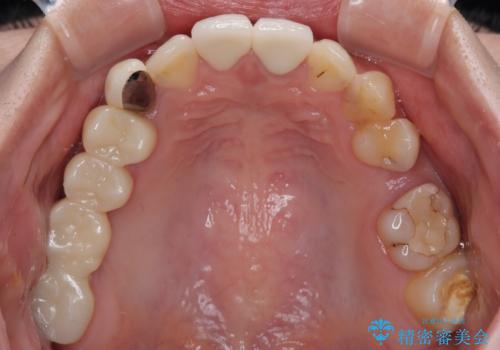

- むし歯により神経を取り除く処置をした歯と隣接する歯の捻れを気にして来院された患者様です。

神経を取り除いた歯は変色が始まっており、隣の歯は捻れにより突出している印象であったので、前歯2歯をオールセラミッククラウンにて補綴することとしました。

捻れている歯は、神経が露出する可能性があり、その場合には根管治療が必要となります。